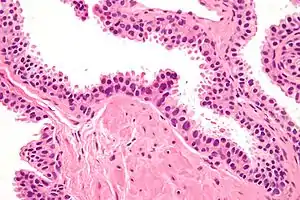

| Micrograph showing high-grade prostatic intraepithelial neoplasia. H&E stain. | |

Its cytologic features are that of prostatic adenocarcinoma:

- presence of nucleoli,

- increased nuclear-to-cytoplasmic ratio and,

- increased nuclear size.

Microscopically, PIN is a collection of irregular, atypical epithelial cells. The architecture of the glands and ducts remains normal. The epithelial cells proliferate and crowding results in a pseudo-multilayer appearance. They remain fully contained within a prostate acinus (the berry-shaped termination of a gland, where the secretion is produced) or duct. The latter can be demonstrated with special staining techniques (immunohistochemistry for cytokeratins) to identify the basal cells forming the supporting layer of the acinus. In prostate cancer, the abnormal cells spread beyond the boundaries of the acinus and form clusters without basal cells. In HGPIN, the basal cell layer is disrupted but present. PIN is primarily found in the peripheral zone of the prostate (75-80%), rarely in the transition zone (10-15%) and very rarely in the central zone (5%), a distribution that parallels the zonal distribution for prostate carcinoma.[6]

Several architectural variants of PIN have been described, and many cases have multiple patterns. The main ones are tufting, micropapillary, cribriform, and flat. Although these different appearances may cause confusion with other conditions, they have not been found to be of clinical importance. Rarer types are signet-ring-cell, small-cell-neuroendocrine, mucinous, foamy, inverted, and with squamous differentiation.[3]